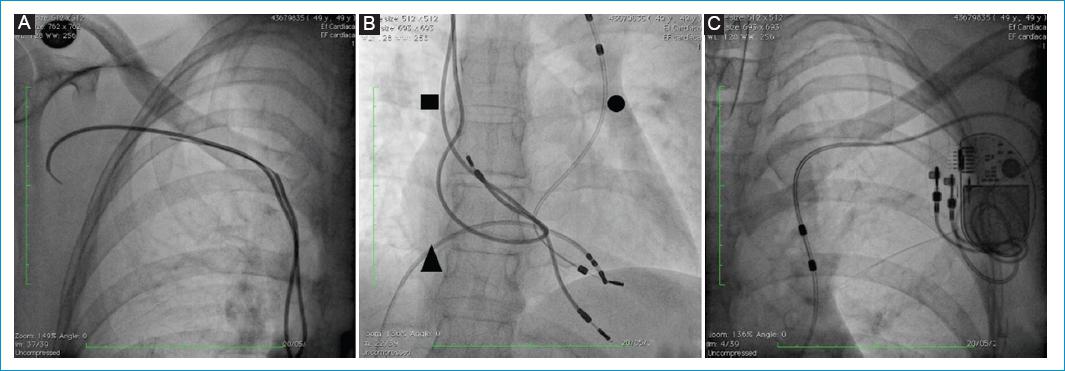

Bajo anestesia general se realizó punción de la vena femoral común derecha y a través de esta se posicionó catéter cuadripolar en el ápex del ventrículo derecho (Fig. 1). Luego, se realizó disección por planos anatómicos hasta la región subpectoral izquierda de donde se explantó el dispositivo y con ayuda de un electrobisturí se liberó el electrodo hasta la región infraclavicular izquierda, posición en la cual se realizó una sutura hemostática. Previa verificación de la integridad del lumen, se cortó el electrodo en la porción distal y a través del lumen se avanzó un Lead Locking Device (LLD) de Spectranetics® (Phillips, Colorado Springs, USA) y sobre este se avanzó vaina de corte rotacional mecánica TightRail 13 Fr de Spectranetics® hasta la porción más proximal del electrodo (pasando por la vena subclavia y la vena cava superior izquierda persistente) y con ayuda de contra-tracción se extrajo casi la totalidad del electrodo, dejando remanente menor de 1 cm (Fig. 2). Antes de retirar la vaina, se avanzó guía 0.032” de 1.5 m, y con técnica de guía retenida se realizó implante de marcapasos bicameral definitivo, sin documentarse estimulación diafragmática a máxima salida (Fig. 3). Debido a que los demás electrodos no estaban generando complicaciones de ningún tipo, no se intentó su extracción.

Figura 1 Imagen en fluoroscopio del dispositivo y los electrodos. A: proyección PA de los electrodos del lado derecho. Están amputados en su extremo distal. B: proyección postero-anterior de silueta cardiaca. Se observan electrodos del lado derecho abandonados (cuadrado negro), electrodo VDD que ingresa por la vena cava superior izquierda persistente (círculo negro) y marcapasos transitorio (triángulo negro). C: proyección PA del electrodo VDD del lado izquierdo. Se observa que el trayecto del electrodo es desde la vena subclavia izquierda e ingresa al corazón por la vena cava superior izquierda persistente.